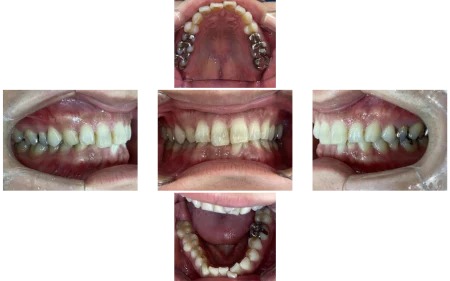

拝見したところ、左下の前歯(中切歯/1番)は歯の並び「歯列」から前に飛び出し、デコボコに並ぶ「叢生(そうせい)」が見られました。

また、上下の歯を噛み合わせた時に、上の前歯が覆いかぶさって下の前歯が見えなくなる深い噛み合わせ「過蓋咬合」でした。

診察の結果、歯を動かすスペースがあり、歯を抜かずに治療できると判断しました。

治療の際は、奥歯を後方に移動させることで、前歯がきれいに並ぶスペースを作りました。

前に1本出ていた前歯は、しっかり歯列におさまりきれいな歯並びになりました。

過蓋咬合も改善し、正しい位置で噛み合わせられるようになりました。